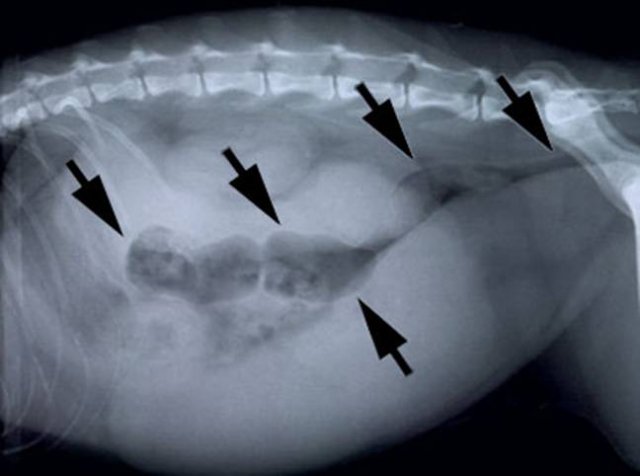

Желудочно-кишечное кровотечение у собаки

Желудочно-кишечное кровотечение у собаки можно заметить невооруженным глазом. У питомца возникают рвотные выделения с кровью, а также кровавые сгустки в кале. У животного могут краснеть глаза, на теле появляются гематомы.